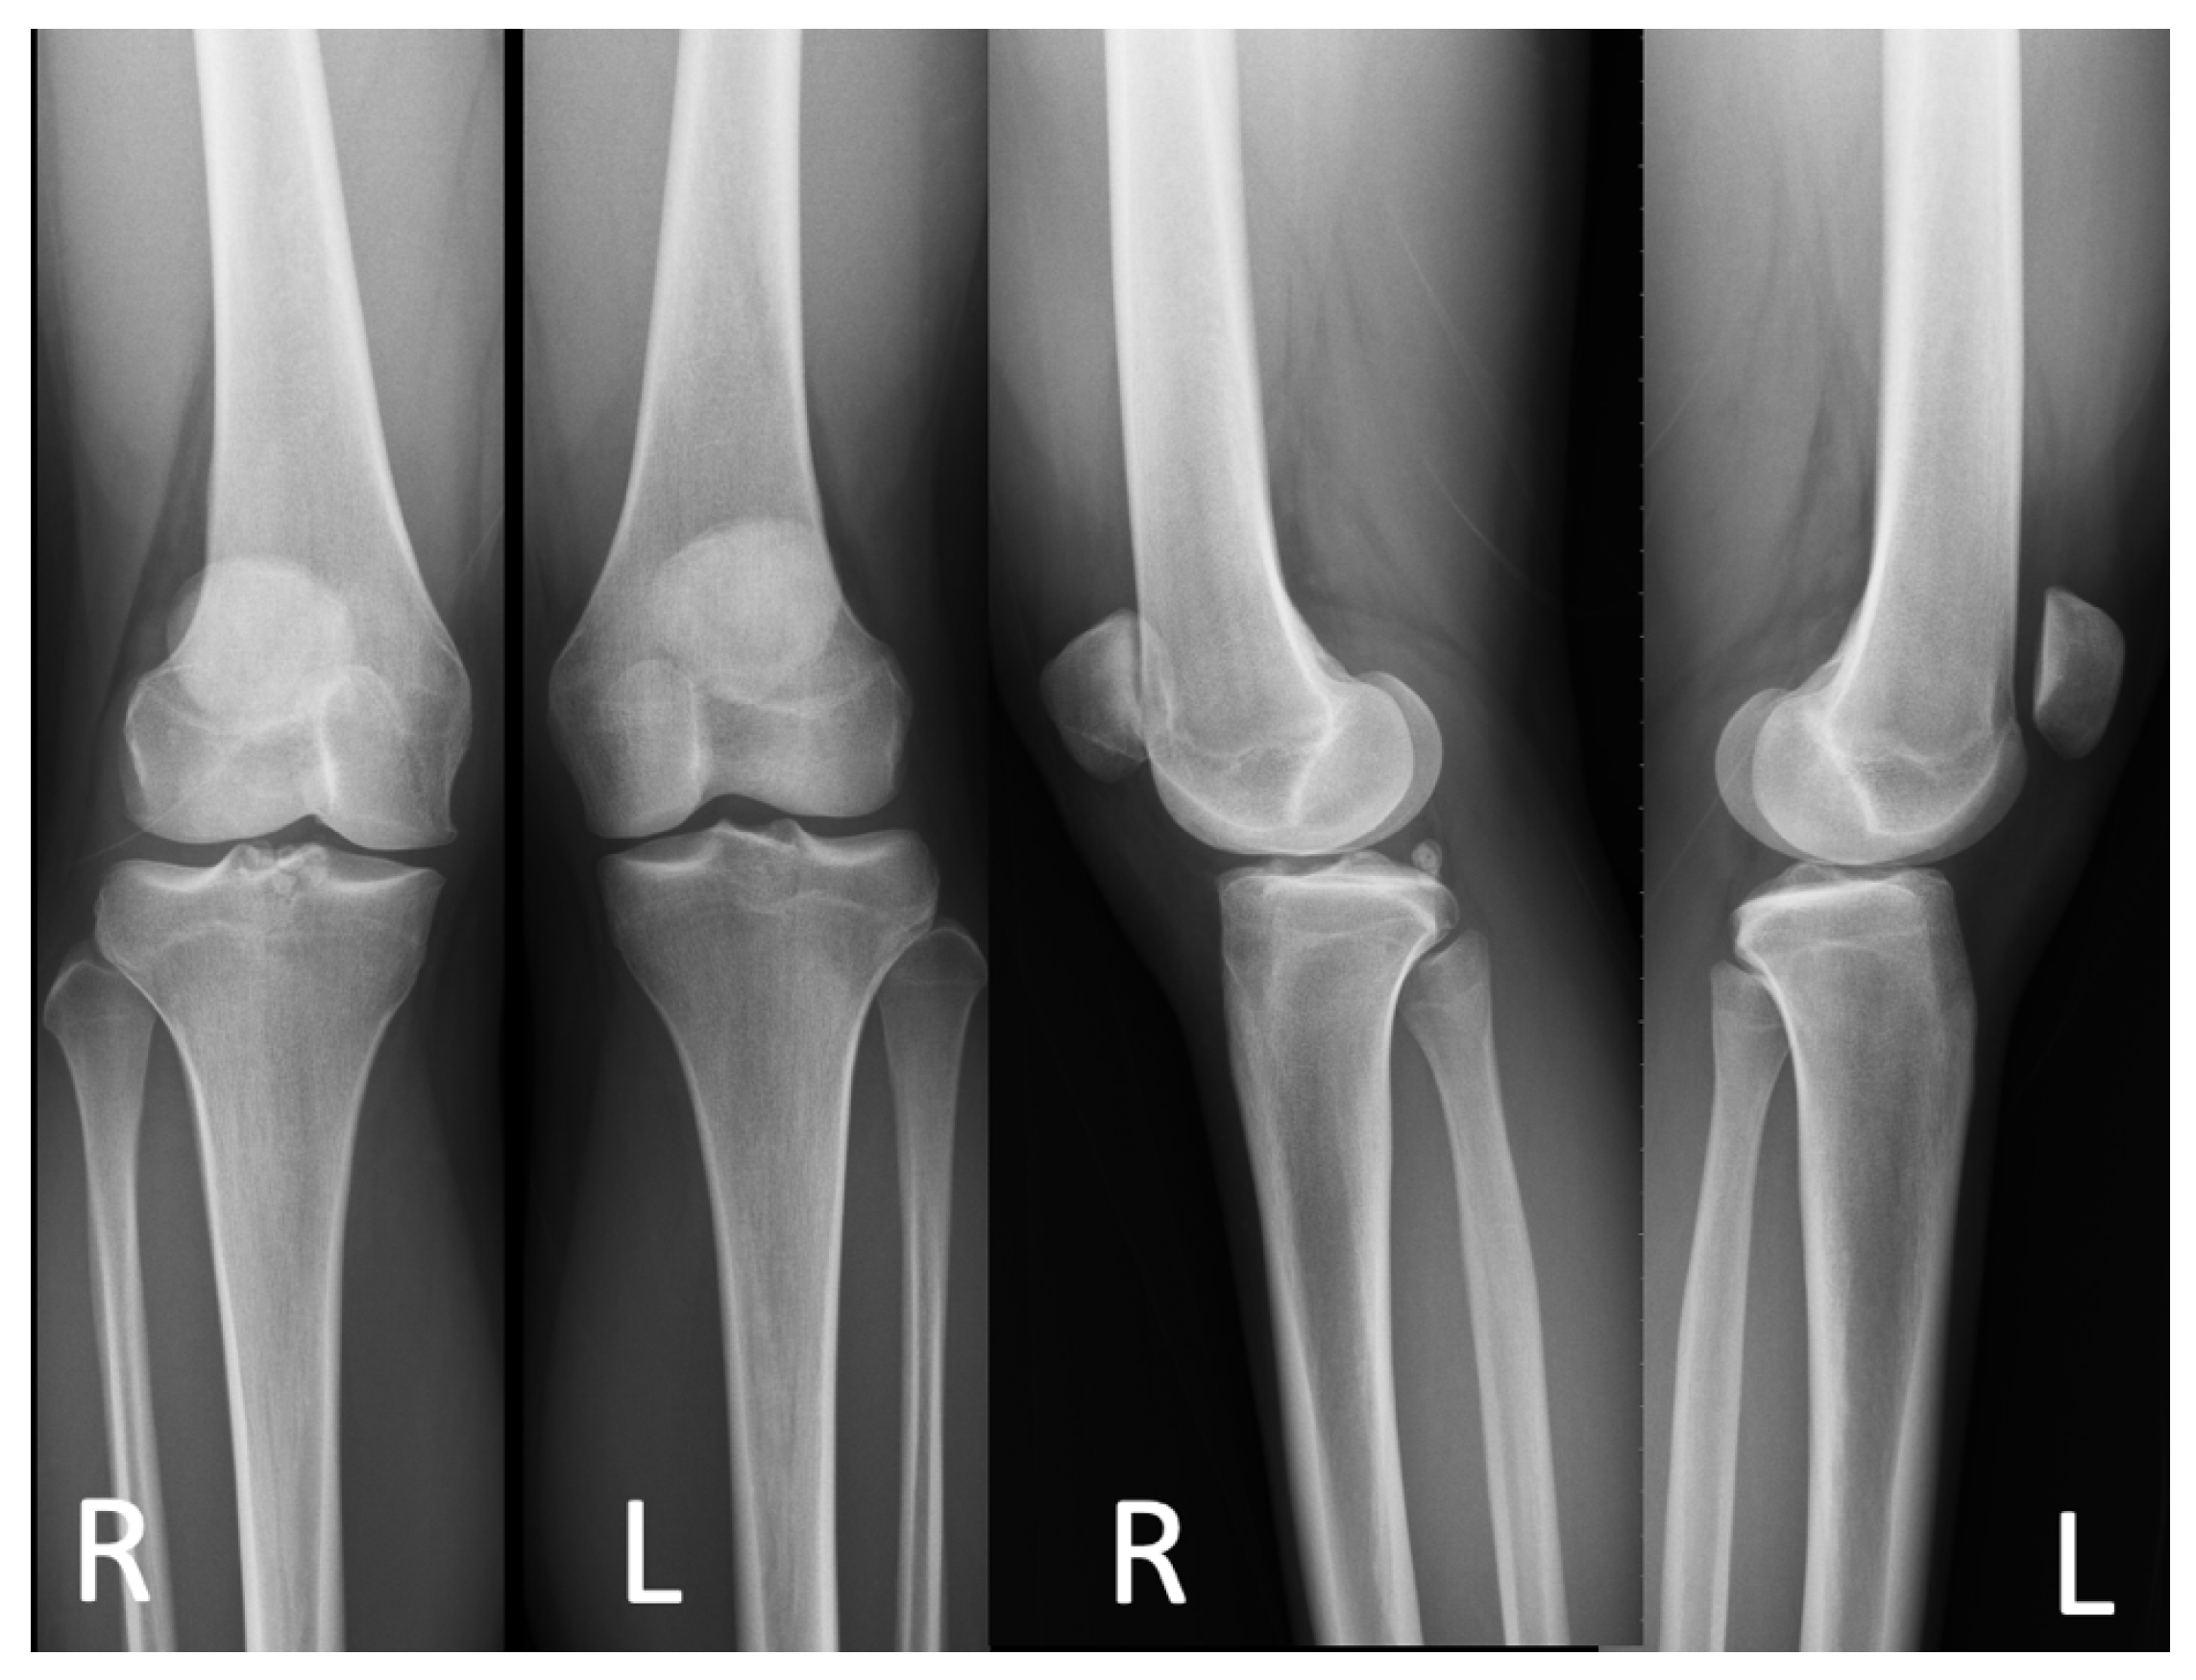

2.1. Case